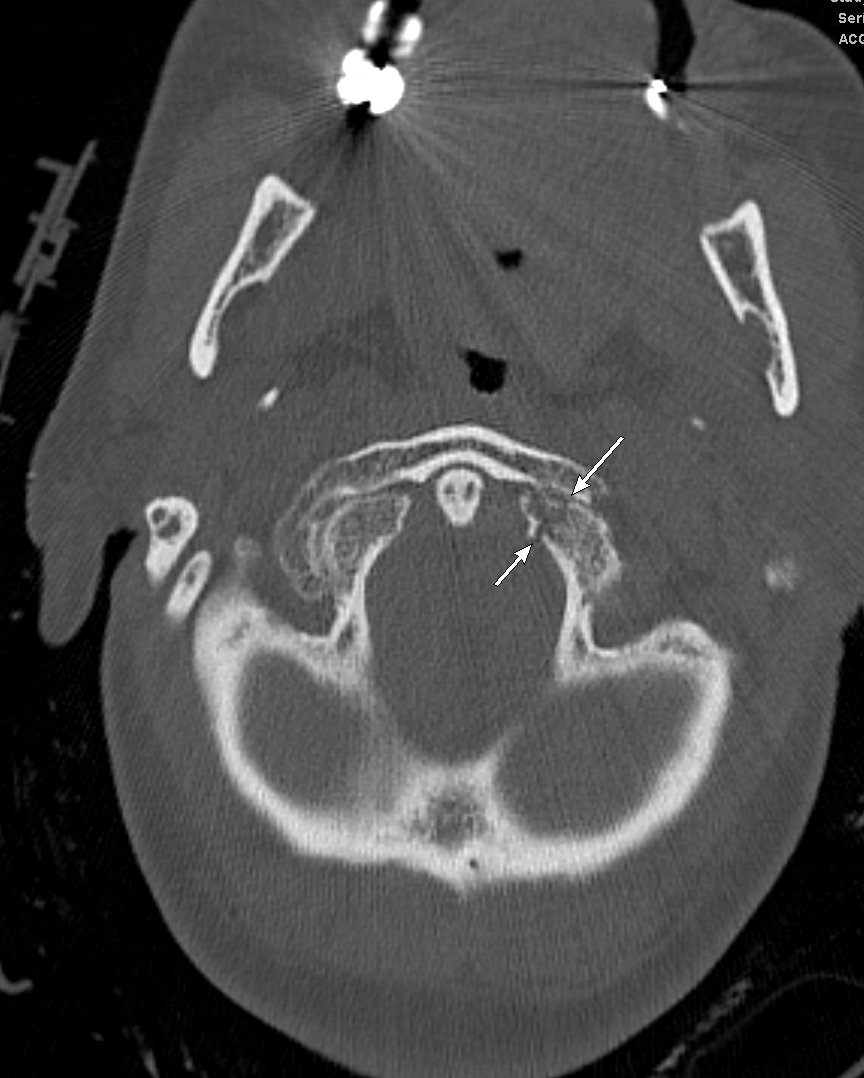

#IUCOTD #187 ANSWER: Traumatic Incudomallear Joint Disarticulation + "Broken Heart" Sign of Wiggins (@rhwiggins)!#FOAMRad#RadRes#MedEd#NeuroRad#HNRad#EMRad Learn more: https://youtu.be/-k7Aw3DGlXQ@IURadiology#COTD#YouTube: https://bit.ly/2EXkWnX#WigginsGetsAnEponym pic.twitter.com/Pq9y0FGmhF

#IUCOTD #187: Trauma, Hearing Loss (different patients). Name the sign (coronal image). Diagnosis?#FOAMrad#RadRes#MedEd#HNRad#EMRad#NeuroRad Answer w/ appropriate GIF ONLY -- stay professional & don't spoil answer!@IURadiology#IUCOTD#YouTube: https://bit.ly/2EXkWnX pic.twitter.com/s2TnVtgl2f